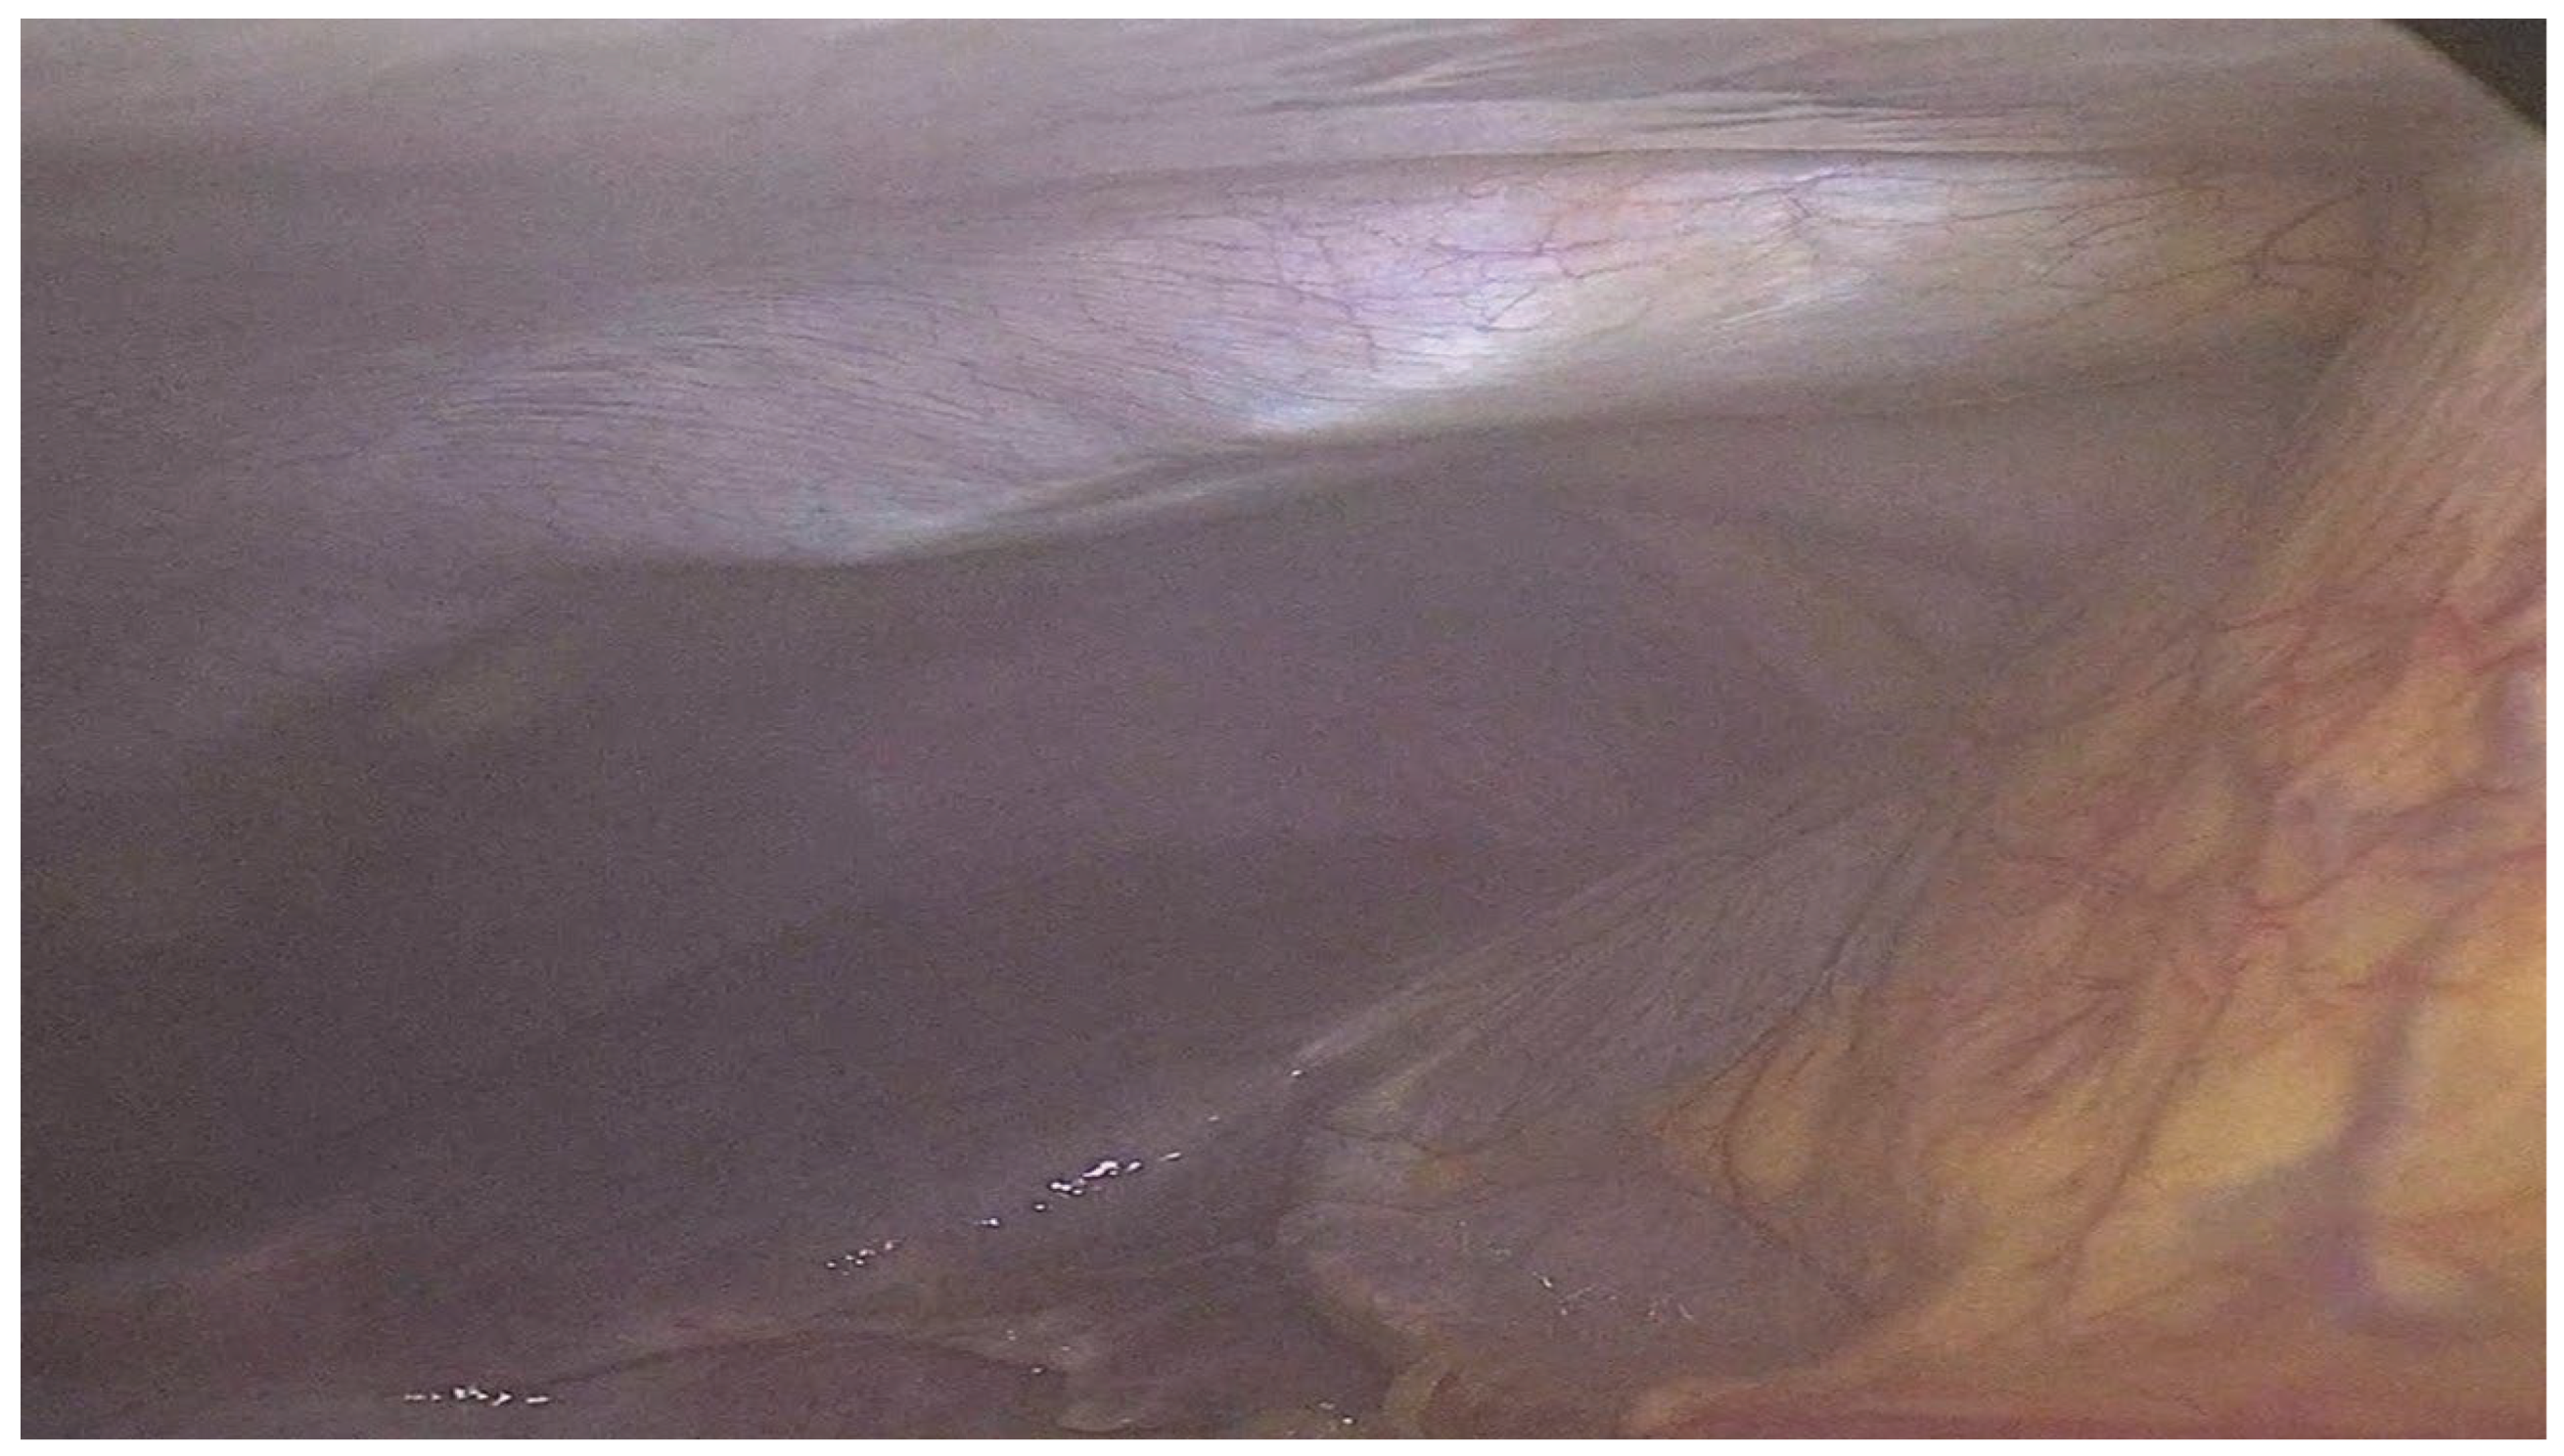

After insufflation, a laparoscopic-guided subcostal TAP block was performed using 20 mL of 0.25% bupivacaine injected into the subxiphoid area to cover the right subcostal region. The needle was advanced to the junction of the posterior rectus sheath and the transversus abdominis muscle, and correct placement was confirmed by visualization of Doyle’s bulge (Figure 1) under laparoscopic vision, indicating accurate fascial plane infiltration as previously described [10]. Following the block, three 5-mm ports were inserted along the right subcostal margin, and standard laparoscopic cholecystectomy was completed.

Figure 1. Illustration of Doyle’s Bulge Observed During Laparoscopic-Guided Subcostal Transversus Abdominis Plane (TAP) Block.